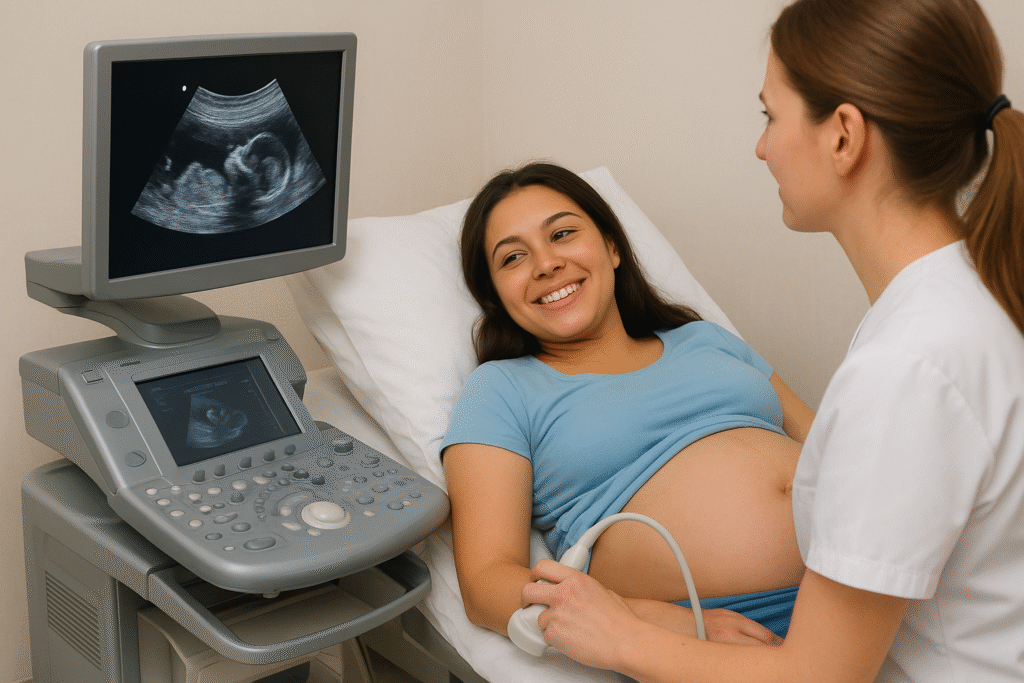

| নাগা বাজার হেলথ সেন্টার গর্ভবতী নারীর জন্য আল্ট্রাসাউন্ড পরীক্ষার গুরুত্ব ও প্রয়োজনীয়তা ঠিকানা: নাগা বাজার, কিনুরমোড়, কাটিলা, বাগমারা, রাজশাহী পরিচালনায়: নাগা বাজার হেলথ সেন্টার সেবা: মাতৃত্বকালীন স্বাস্থ্যসেবা, আল্ট্রাসাউন্ড পরীক্ষা, পরামর্শ, ও চিকিৎসা ভূমিকা গর্ভাবস্থা একজন নারীর জীবনের সবচেয়ে সংবেদনশীল ও মূল্যবান সময়। এই সময়ে মায়ের শরীরে নানা পরিবর্তন ঘটে এবং সেই সঙ্গে শিশুরও শুরু হয় নতুন জীবনের বিকাশ। মা ও শিশুর উভয়ের নিরাপত্তা, স্বাস্থ্য ও বিকাশ পর্যবেক্ষণের জন্য আধুনিক চিকিৎসা ব্যবস্থায় আল্ট্রাসাউন্ড পরীক্ষা এক অপরিহার্য অংশ। আল্ট্রাসাউন্ড হলো এমন এক প্রযুক্তি যা কোনো ক্ষতি না করেই মায়ের গর্ভের ভেতরের অবস্থা স্পষ্টভাবে দেখায়। এটি মায়ের ও শিশুর জীবনের জন্য অমূল্য এক সেবা। আজ আমরা বিস্তারিত জানব কেন আল্ট্রাসাউন্ড পরীক্ষা দরকার, কীভাবে এটি করা হয়, এবং যদি এটি না করা হয় তবে কী কী বিপদ হতে পারে। আল্ট্রাসাউন্ড কী এবং এটি কীভাবে কাজ করে আল্ট্রাসাউন্ড একটি সাউন্ড-ওয়েভ ভিত্তিক পরীক্ষা। এতে মেশিন থেকে নির্গত উচ্চ কম্পাঙ্কের শব্দ তরঙ্গ গর্ভের ভেতরে প্রবেশ করে এবং শিশুর শরীরের বিভিন্ন অঙ্গ থেকে প্রতিফলিত হয়ে ফিরে আসে। এই প্রতিফলিত তরঙ্গগুলো কম্পিউটার স্ক্রিনে ছবির আকারে দেখা যায়। এই ছবিকে বলা হয় সোনোগ্রাম (Sonogram)। চিকিৎসক এই সোনোগ্রামের মাধ্যমে শিশুর হৃদস্পন্দন, অঙ্গ-প্রত্যঙ্গের গঠন, ওজন, অবস্থান, এবং অন্যান্য জটিলতা পর্যবেক্ষণ করতে পারেন। আল্ট্রাসাউন্ড পরীক্ষার উদ্দেশ্য ও গুরুত্ব আল্ট্রাসাউন্ড কেবলমাত্র শিশুর ছবি দেখার জন্য নয়— এটি মা ও শিশুর জীবনের নিরাপত্তা নিশ্চিত করার জন্য অপরিহার্য একটি ধাপ। নিচে এর মূল উদ্দেশ্যগুলো ব্যাখ্যা করা হলোঃ ১️⃣ গর্ভাবস্থার নিশ্চিতকরণ প্রথম দিকে আল্ট্রাসাউন্ডের মাধ্যমে দেখা যায় ভ্রূণটি সত্যিই জরায়ুর ভিতরে আছে কিনা। অনেক সময় একটোপিক প্রেগন্যান্সি (Ectopic Pregnancy) অর্থাৎ ভ্রূণ জরায়ুর বাইরে তৈরি হয়, যা জীবনহানিকর হতে পারে। এই সমস্যা শুধুমাত্র আল্ট্রাসাউন্ডের মাধ্যমেই ধরা সম্ভব। ২️⃣ ভ্রূণের সংখ্যা নির্ধারণ একাধিক শিশু গর্ভে আছে কিনা— যেমন যমজ (Twins) বা ত্রিপলেট (Triplets)— তা আল্ট্রাসাউন্ড ছাড়া জানা যায় না। আগেভাগে জানলে চিকিৎসক ও পরিবার উভয়ে প্রস্তুতি নিতে পারেন। ৩️⃣ গর্ভকাল নির্ধারণ (Gestational Age) প্রথম বা দ্বিতীয় মাসে আল্ট্রাসাউন্ডে শিশুর আকার দেখে কত সপ্তাহের গর্ভ তা নির্ধারণ করা যায়। এর ফলে শিশুর সম্ভাব্য জন্ম তারিখ (EDD) নির্ভুলভাবে জানা যায়, যা প্রসব পরিকল্পনার জন্য গুরুত্বপূর্ণ। ৪️⃣ শিশুর হৃদস্পন্দন ও বৃদ্ধি দেখা আল্ট্রাসাউন্ডে শিশুর হৃদস্পন্দন, হাত-পা নড়াচড়া, হাড়ের বৃদ্ধি ও মস্তিষ্কের গঠন দেখা যায়। এর মাধ্যমে বোঝা যায় শিশুটি সুস্থভাবে বেড়ে উঠছে কিনা। ৫️⃣ প্লাসেন্টার অবস্থান নির্ধারণ শিশুর খাদ্য ও অক্সিজেন সরবরাহের জন্য জরায়ুর ভেতরে প্লাসেন্টা গুরুত্বপূর্ণ ভূমিকা রাখে। অনেক সময় প্লাসেন্টা নিচের দিকে অবস্থান করে (Placenta Previa), যা প্রসবের সময় অতিরিক্ত রক্তপাতের কারণ হতে পারে। আল্ট্রাসাউন্ডে এই অবস্থা আগেই জানা যায়। ৬️⃣ অ্যামনিওটিক ফ্লুইড পরিমাপ শিশুর চারপাশে থাকা অ্যামনিওটিক ফ্লুইড তার বিকাশের জন্য অপরিহার্য। এর পরিমাণ বেশি বা কম হলে জটিলতা তৈরি হয়। আল্ট্রাসাউন্ডে সহজেই এই পরিমাণ মাপা যায়। ৭️⃣ শিশুর গঠনগত ত্রুটি (Structural Anomalies) ১৮–২০ সপ্তাহে করা আল্ট্রাসাউন্ডে দেখা যায় শিশুর অঙ্গপ্রত্যঙ্গ স্বাভাবিকভাবে গঠিত হয়েছে কিনা। এতে জন্মগত বিকৃতি যেমন— হৃদরোগ, মস্তিষ্কের ত্রুটি, ঠোঁট কাটা, ইত্যাদি আগেভাগে ধরা পড়ে। ৮️⃣ শিশুর অবস্থান নির্ণয় প্রসবের সময় শিশুর অবস্থান খুব গুরুত্বপূর্ণ। যদি শিশুর মাথা নিচের দিকে থাকে তবে স্বাভাবিক প্রসব সম্ভব, অন্যথায় সিজারিয়ান দরকার হয়। আল্ট্রাসাউন্ডে এটি নিশ্চিত করা যায়। ৯️⃣ শিশুর বৃদ্ধি ও সুস্থতা (Fetal Growth & Well-being) শেষ ত্রৈমাসিকে (৩০ সপ্তাহের পর) আল্ট্রাসাউন্ডে দেখা হয় শিশুর ওজন, নড়াচড়া, রক্তসঞ্চালন ও হার্টবিট ঠিক আছে কিনা। এটি মা ও শিশুর সুস্থতা নিশ্চিত করে। প্রসবের প্রস্তুতি ও নিরাপত্তা আল্ট্রাসাউন্ড রিপোর্ট দেখে চিকিৎসক নির্ধারণ করেন প্রসবের উপযুক্ত সময় ও পদ্ধতি। এতে আকস্মিক জটিলতা বা অপ্রত্যাশিত ঝুঁকি কমে যায়। গর্ভাবস্থায় কখন আল্ট্রাসাউন্ড করা উচিত চিকিৎসকের পরামর্শ অনুযায়ী সাধারণত নিচের সময়গুলোতে আল্ট্রাসাউন্ড করা হয়ঃ পর্যায় সময়কাল উদ্দেশ্য ১ম ট্রাইমেস্টার ৬–১২ সপ্তাহ গর্ভাবস্থা নিশ্চিতকরণ, শিশুর সংখ্যা ও অবস্থান ২য় ট্রাইমেস্টার ১৮–২২ সপ্তাহ শিশুর গঠনগত ত্রুটি, প্লাসেন্টা ও ফ্লুইড পরীক্ষা ৩য় ট্রাইমেস্টার ৩০–৩৬ সপ্তাহ শিশুর ওজন, অবস্থান ও প্রসবের প্রস্তুতি যাচাই বিশেষ রোগ যেমন উচ্চ রক্তচাপ, ডায়াবেটিস, রক্তপাত, বা আগের গর্ভপাতের ইতিহাস থাকলে চিকিৎসক অতিরিক্ত আল্ট্রাসাউন্ড পরামর্শ দিতে পারেন। আল্ট্রাসাউন্ড না করলে যে ঝুঁকি ও সমস্যা দেখা দিতে পারে অনেকে মনে করেন আল্ট্রাসাউন্ড জরুরি নয়, কিন্তু এই পরীক্ষা না করলে মা ও শিশুর উভয়ের জীবনে মারাত্মক সমস্যা তৈরি হতে পারে। ১️⃣ একটোপিক প্রেগন্যান্সি শনাক্ত না হওয়া জরায়ুর বাইরে ভ্রূণ তৈরি হলে তা জীবনঘাতী হতে পারে। আল্ট্রাসাউন্ড না করলে টিউব ফেটে গিয়ে রক্তপাত ও মৃত্যুও হতে পারে। ২️⃣ জন্মগত বিকৃতি অজানা থাকা যদি শিশুর কোনো জন্মগত সমস্যা থাকে, তা আগেভাগে জানা না গেলে পরবর্তী চিকিৎসা বা প্রস্তুতি অসম্ভব হয়ে পড়ে। ৩️⃣ প্লাসেন্টার অবস্থানজনিত রক্তপাত Placenta Previa থাকলে প্রসবের সময় অতিরিক্ত রক্তপাত হয়। আগেভাগে জানা না গেলে এটি মা ও শিশুর প্রাণঘাতী হতে পারে। ৪️⃣ শিশুর বৃদ্ধি থেমে যাওয়া শিশু স্বাভাবিক হারে না বাড়লে তা আল্ট্রাসাউন্ডেই বোঝা যায়। পরীক্ষা না করলে শিশুটি অপুষ্ট বা অকাল জন্ম নিতে পারে। ৫️⃣ অ্যামনিওটিক ফ্লুইডের ভারসাম্যহীনতা অতিরিক্ত বা কম তরল শিশুর শ্বাসনালী ও নড়াচড়া বাধাগ্রস্ত করতে পারে, যা প্রাণঘাতী হতে পারে। ৬️⃣ শিশুর ভুল অবস্থান অজানা থাকা শেষের দিকে শিশুর মাথা উল্টো থাকলে স্বাভাবিক প্রসব ঝুঁকিপূর্ণ। আল্ট্রাসাউন্ড না করলে তা বোঝা যায় না। ৭️⃣ শিশুর মৃত্যু বা নড়াচড়া বন্ধ হওয়া শনাক্ত না হওয়া আল্ট্রাসাউন্ড না করলে অনেক সময় মৃত ভ্রূণ জরায়ুর ভেতরে থেকে যায়, যা সংক্রমণ ও গুরুতর জটিলতার কারণ হয়। ৮️⃣ যমজ শিশুর সঠিক যত্ন না পাওয়া দুই বা তিন শিশুর গর্ভে একটির বৃদ্ধি কমে গেলে তা বোঝা যায় না এবং শিশুটি মারা যেতে পারে। ৯️⃣ প্রসবের সময় প্রস্তুতির অভাব শিশুর আকার, অবস্থান ও প্লাসেন্টা সম্পর্কে অজানা থাকলে প্রসবের সময় জটিলতা বাড়ে, যা জরুরি অস্ত্রোপচার ডেকে আনতে পারে। ভুল তারিখ ও চিকিৎসা পরিকল্পনা আল্ট্রাসাউন্ড ছাড়া গর্ভকাল ভুল গণনা হলে প্রসব আগেভাগে বা দেরিতে হতে পারে— উভয় অবস্থাতেই শিশুর জীবন ঝুঁকিতে পড়ে। আল্ট্রাসাউন্ড সম্পর্কে কিছু সাধারণ ভুল ধারণা “আল্ট্রাসাউন্ডে বিকিরণ থাকে” — ভুল। এতে কোনো ক্ষতিকর রশ্মি ব্যবহার হয় না।“বারবার করলে শিশুর ক্ষতি হয়” — ভুল। চিকিৎসকের পরামর্শে করলে কোনো ক্ষতি হয় না।“এটি ব্যয়বহুল ও অপ্রয়োজনীয়” — ভুল। এখন বাংলাদেশের প্রায় প্রতিটি ক্লিনিকে সাশ্রয়ী মূল্যে আল্ট্রাসাউন্ড সুবিধা পাওয়া যায়। চিকিৎসকের বিশেষ পরামর্শ প্রথম ৬–৮ সপ্তাহের মধ্যে আল্ট্রাসাউন্ড করুন।পরবর্তী পর্যায়ে নির্দিষ্ট সময়ে পুনরায় পরীক্ষা করুন।যেকোনো অস্বাভাবিক উপসর্গ যেমন— ব্যথা, রক্তপাত, বা শিশুর নড়াচড়া বন্ধ হয়ে যাওয়া— ঘটলে জরুরি আল্ট্রাসাউন্ড করুন।শুধুমাত্র প্রশিক্ষিত টেকনিশিয়ান ও চিকিৎসকের অধীনে পরীক্ষা করুন।রিপোর্ট অবশ্যই গাইনোকোলজিস্টকে দেখান। নাগা বাজার হেলথ সেন্টারের পক্ষ থেকে বার্তা “নাগা বাজার হেলথ সেন্টার”, নাগা বাজার, কিনুরমোড়, কাটিলা, বাগমারা, রাজশাহী স্থানীয় জনগণের জন্য আধুনিক স্বাস্থ্যসেবার এক নতুন দিগন্ত খুলে দিতে কাজ করছে। আমাদের উদ্দেশ্য— প্রতিটি গর্ভবতী মা যেন নিরাপদ মাতৃত্ব ও সুস্থ শিশুর জন্মের নিশ্চয়তা পান। এখানে পরিকল্পনা রয়েছে— আধুনিক আল্ট্রাসাউন্ড সেবাঅভিজ্ঞ স্ত্রীরোগ বিশেষজ্ঞ দ্বারা পরামর্শপ্রসূতি ও নবজাতক সেবাঅনলাইন ও সরাসরি অ্যাপয়েন্টমেন্ট ব্যবস্থা উপসংহার গর্ভাবস্থায় আল্ট্রাসাউন্ড পরীক্ষা কোনো বিলাসিতা নয়— এটি মায়ের ও শিশুর জীবনরক্ষাকারী পরীক্ষা। এটি মা ও শিশুর মধ্যে এক অদৃশ্য সেতুবন্ধন তৈরি করে— যার মাধ্যমে জানা যায় শিশুর হৃদস্পন্দন, হাসি, ও বৃদ্ধি ঠিকঠাক আছে কিনা। সঠিক সময়ে আল্ট্রাসাউন্ড পরীক্ষা করা মানে— “নিজের যত্ন নিন, আপনার সন্তানের জন্য আজই আল্ট্রাসাউন্ড করান।” প্রস্তুতকারক: নাগা বাজার হেলথ সেন্টার ইনফরমেশন টিম প্রকাশিত: নাগা বাজার, কিনুরমোড়, কাটিলা, বাগমারা, রাজশাহী ওয়েবসাইট: www.nagabazarshoppingcentre.com |